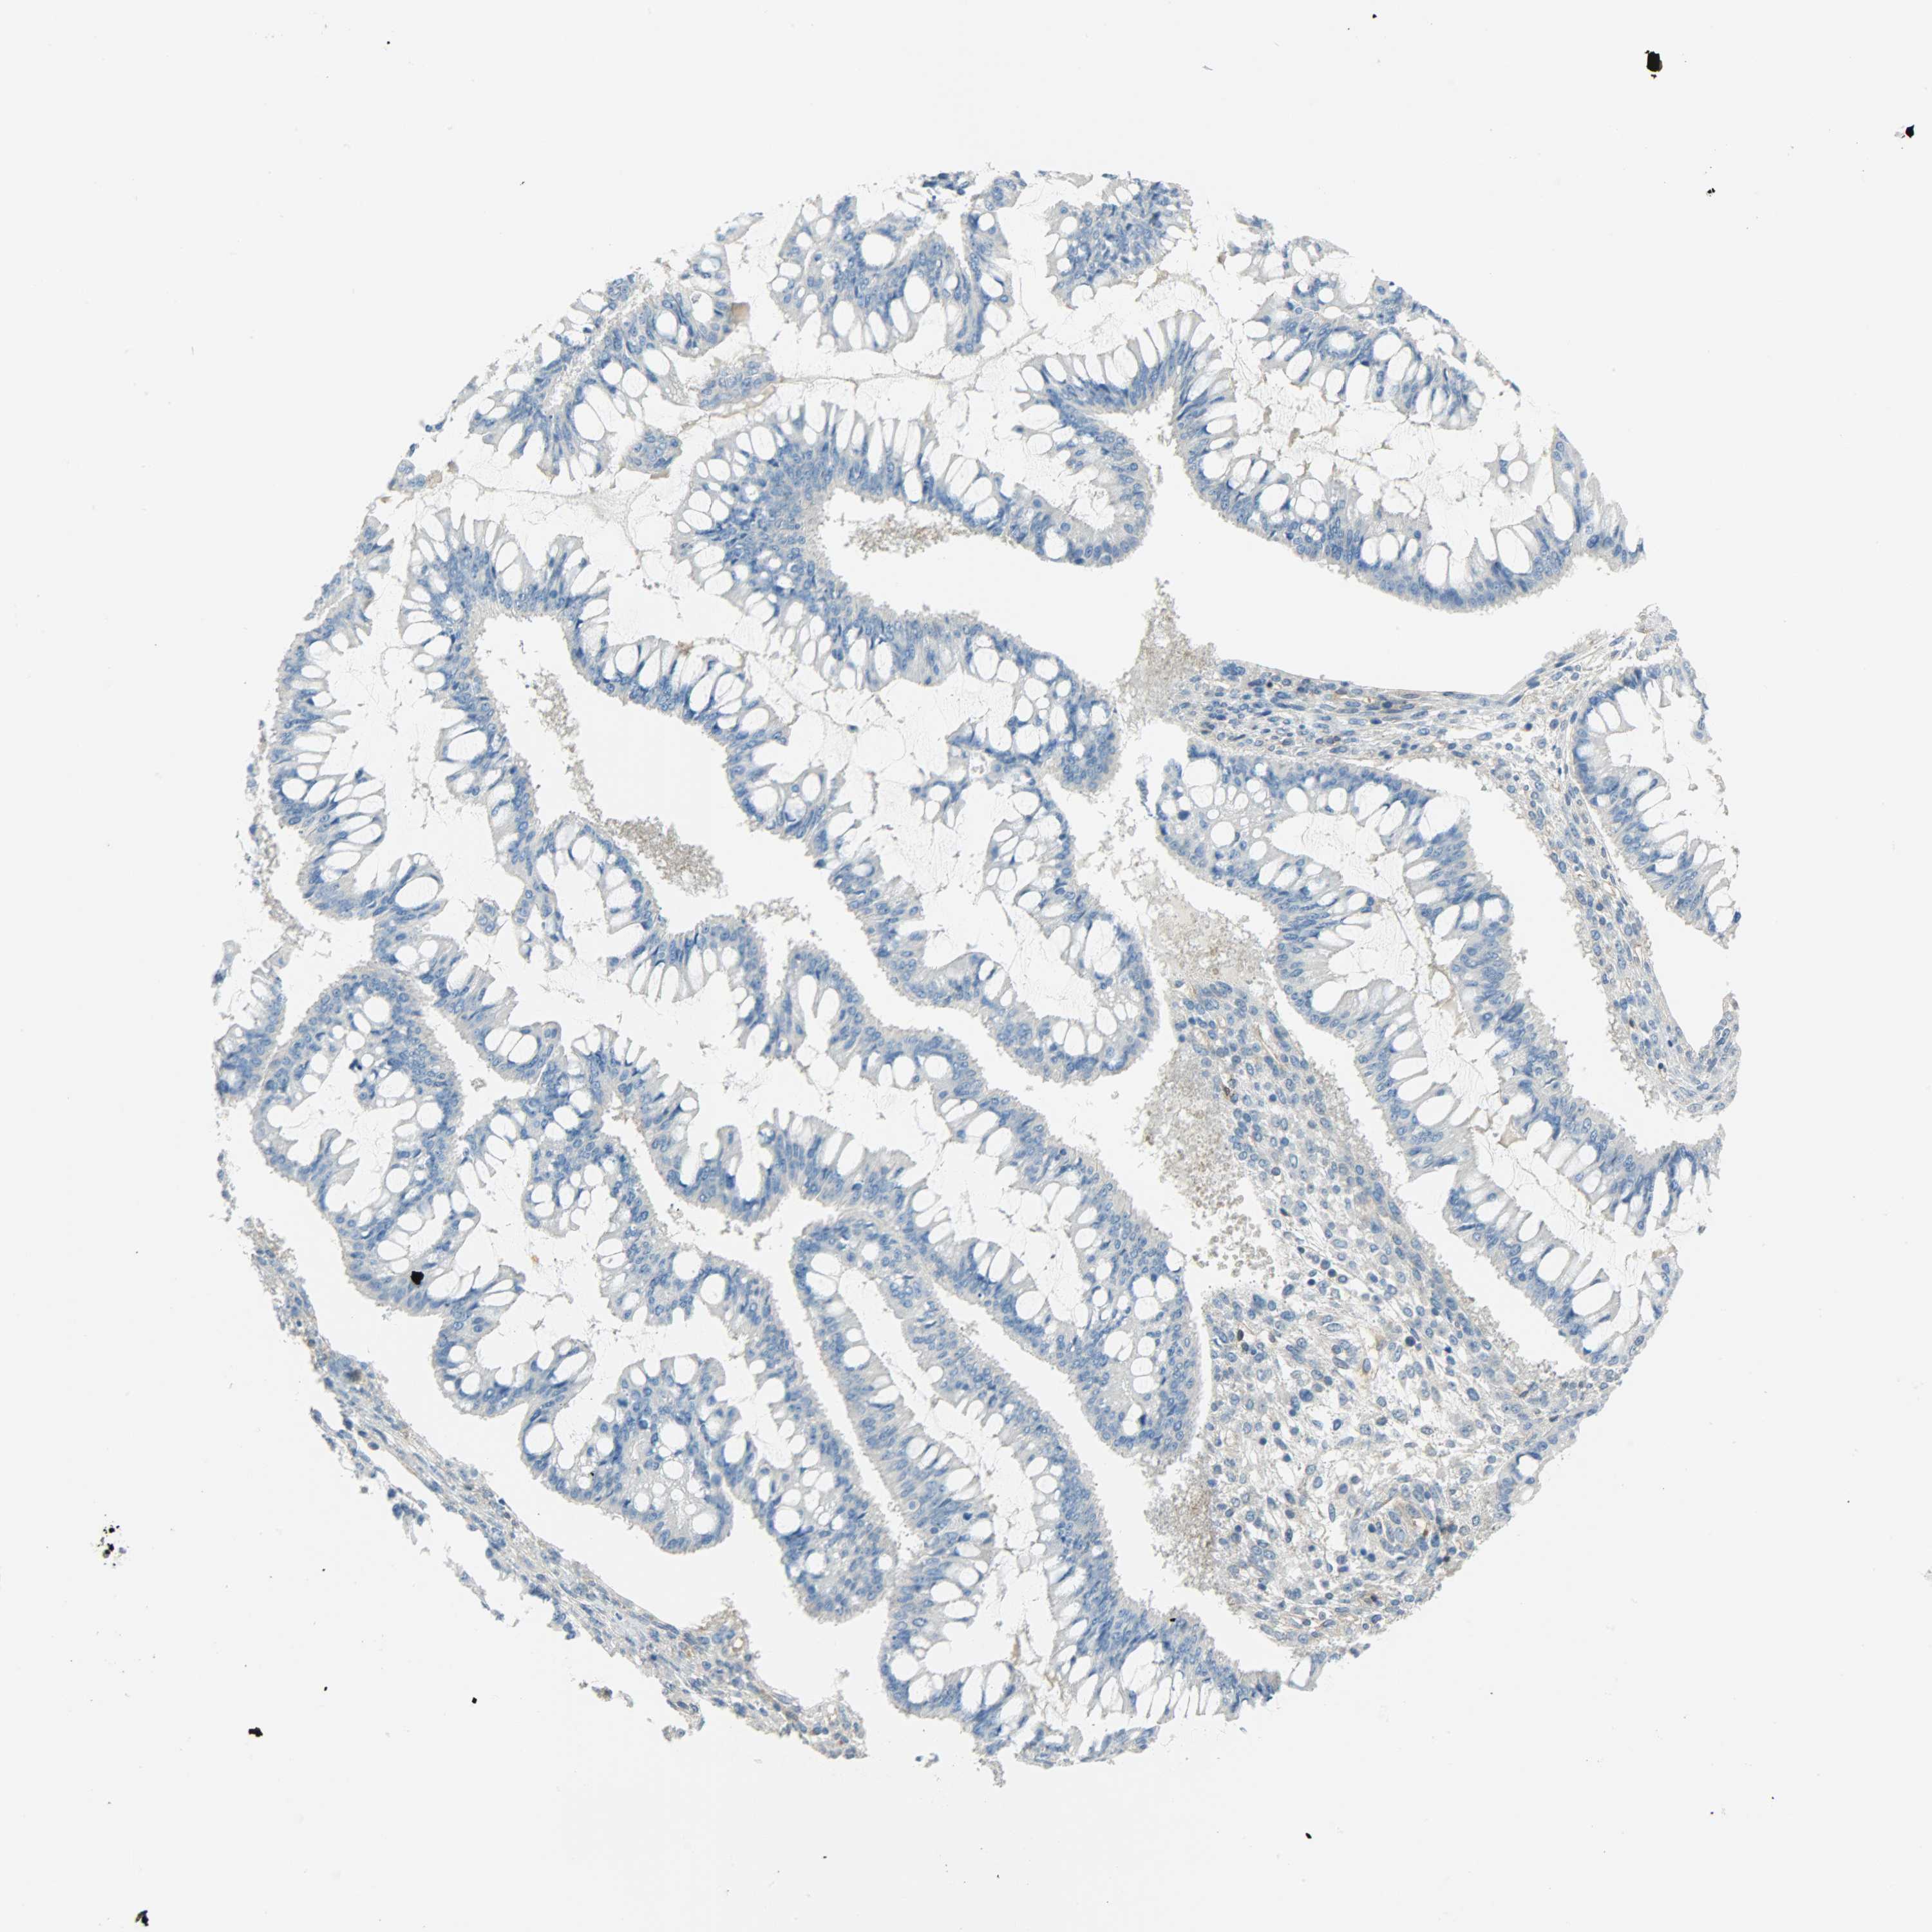

OVARIAN CANCER - Protein expressioni

A mouse-over function shows sample information and annotation data. Click on an image to view it in a full screen mode. Samples can be filtered based on level of antibody staining by selecting one or several of the following categories: high, medium, low and not detected. The assay and annotation is described here.

Note that samples used for immunohistochemistry by the Human Protein Atlas do not correspond to samples in the TCGA dataset.

Antibody stainingi

Antibody staining in the annotated cell types in the current human tissue is reported as not detected, low, medium, or high, based on conventional immunohistochemistry profiling in selected tissues. This score is based on the combination of the staining intensity and fraction of stained cells.

Each image is clickable and will lead to virtual microscopy that enables deeper exploration of all samples and also displays staining intensity scores, fraction scores and subcellular localization as well as patient and tissue information for each sample.

Antibody HPA004926

Staining

High

Medium

Low

Not detected

Intensity

Strong

Moderate

Weak

Negative

Quantity

>75%

75%-25%

<25%

None

Location

Nuclear

Cytoplasmic/membranous

Cytoplasmic/membranous,nuclear

Cystadenocarcinoma, serous, NOS

Carcinoma, endometroid

Carcinoma, NOS

Cystadenocarcinoma, mucinous, NOS